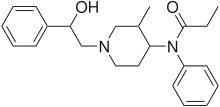

Anilidopiperidines